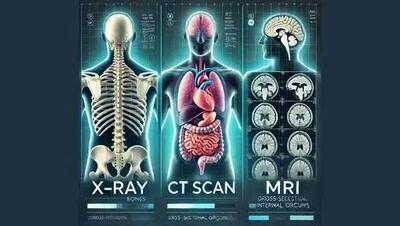

اشعه ایکس

اسکن اشعه ایکس به معمای چگونگی قرار گرفتن تابوت بدون دریچه لیدی چنت پاسخ میدهد.

پروفسور Pu Kanyi نویسنده ارشد و همکار این مطالعه گفت: «ما از دوزهای بسیار پایین اشعه ایکس و MRAPهای کشنده سرطان استفاده کردیم.